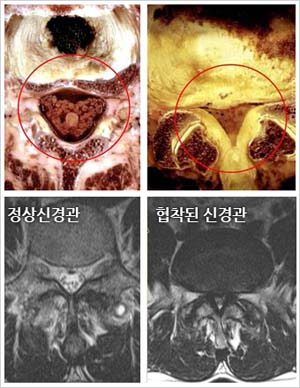

오늘 글에서는 척추관 협착증 증상 치료방법에 대해서 알아보도록 하겠어요. 척추관 협착증은 퇴행성 디스크와 아울러 전형적인 퇴행성 척추질환입니다. 척추의 퇴행이 오래 진행되어 인대가 두꺼워지고 붓게 된다면 신경구멍이 좁아지며 척추관 협착증이 유발되요.

척추 관절과 인대가 변경되고 두꺼워져 척추 신경을 조이면 신경의 혈액순환이 모자라게 되어 생겨해요. 선천적으로 요추관의 정도가 정상보다 작게 만들어지는 경우로, 대개는 35세가 넘어 뼈와 인대의 변환가 연거푸해서 증상이 형성되나 20세 전후의 아주 젊은 나이에도 띄엄띄엄 발견되요.

최고 많이 보이는 원인으로 척추 퇴행성 골관절염이 생김에 따라 허리 관절의 정도가 많아지고 인대도 두꺼워지는 더불어 가시 같은 뼈가 자라나 신경 길을 좁아지게 해요.

척추관 협착증은 척추 관절과 주변 조직의 변화로 인해 나타나는 질환입니다. 이 질환의 원인은 자연적인 단계인 노화로 인한 척추 관절 연골 파괴와 뼈 형태적 전환, 디스크의 노화나 손상, 척추 골절, 척추 관절 염증, 그리고 선천적인 이상 등 각가지 요소들이 복합적으로 활동하여 생겨날수 있고요.

이러한 요소들은 척추관의 좁아짐과 신경 구조에 압력이 가해짐으로써 척추관 협착증을 일으킬 수 있습니다. 개인의 생활 습관, 유전적 요인, 부상 등도 사유로 작용할 수 있으며 각 개인의 경우에는 이러한 요소들이 복합적으로 작용하여 질환을 촉발합니다.